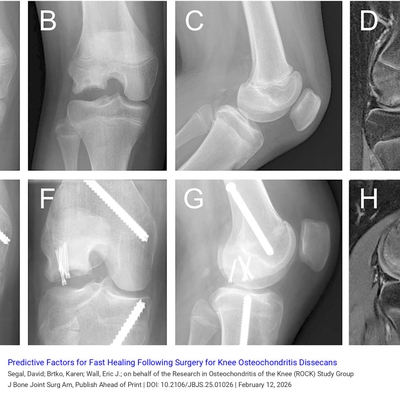

J Bone & Joint Surg